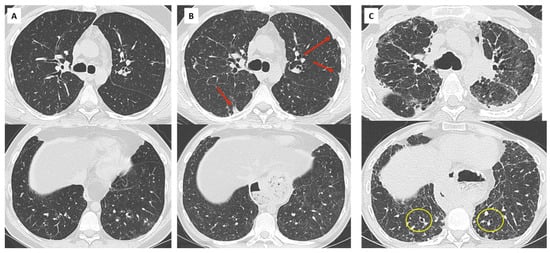

- Verleden, S.E.; Von Der Thüsen, J.; Van Herck, A.; Weynand, B.; Verbeken, E.; Verschakelen, J.; Dubbeldam, A.; Vanaudenaerde, B.M.; Vos, R.; Verleden, G.M.; et al. Identification and characterization of chronic lung allograft dysfunction patients with mixed phenotype: A single-center study. Clin. Transplant. 2020, 34, e13781. [Google Scholar] [CrossRef]

- Dettmer, S.; Shin, H.-O.; Vogel-Claussen, J.; Westphal, M.; Haverich, A.; Warnecke, G.; Welte, T.; Wacker, F.; Gottlieb, J.; Suhling, H. CT at onset of chronic lung allograft dysfunction in lung transplant patients predicts development of the restrictive phenotype and survival. Eur. J. Radiol. 2017, 94, 78–84. [Google Scholar] [CrossRef] [PubMed]

- Byrne, D.; Nador, R.G.; English, J.C.; Yee, J.; Levy, R.; Bergeron, C.; Swiston, J.R.; Mets, O.M.; Muller, N.L.; Bilawich, A.-M. Chronic Lung Allograft Dysfunction: Review of CT and Pathologic Findings. Radiol. Cardiothorac. Imaging 2021, 3, e200314. [Google Scholar] [CrossRef] [PubMed]